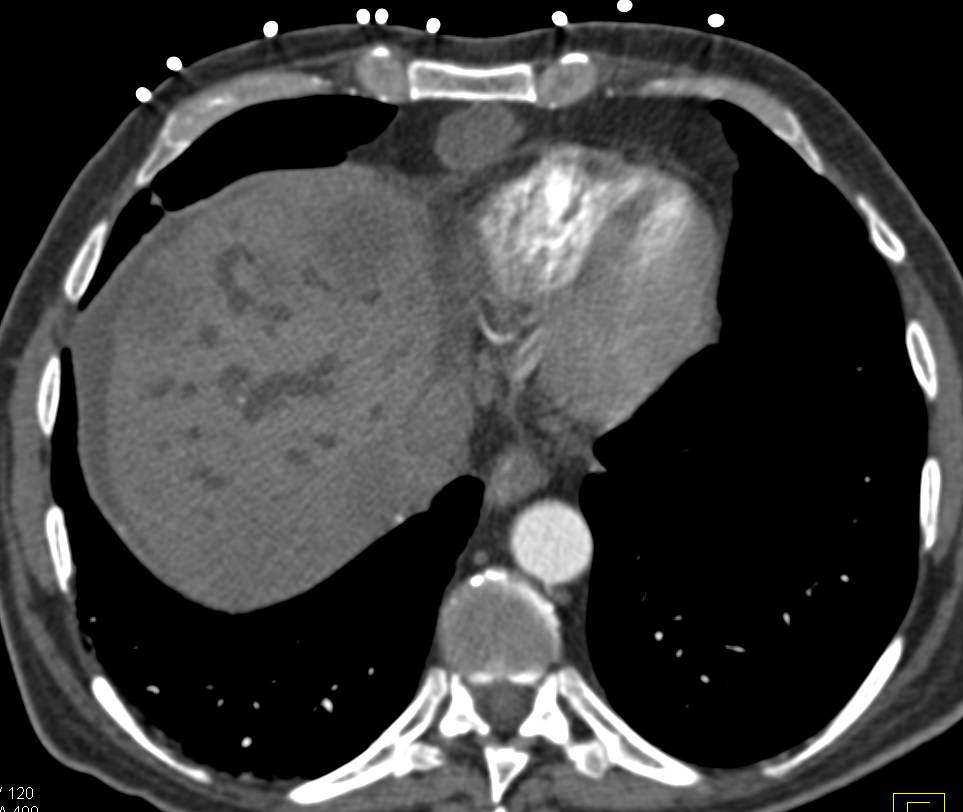

Carcinoid Tumor with Enhancement in the Primary Tumor and Liver Metastases